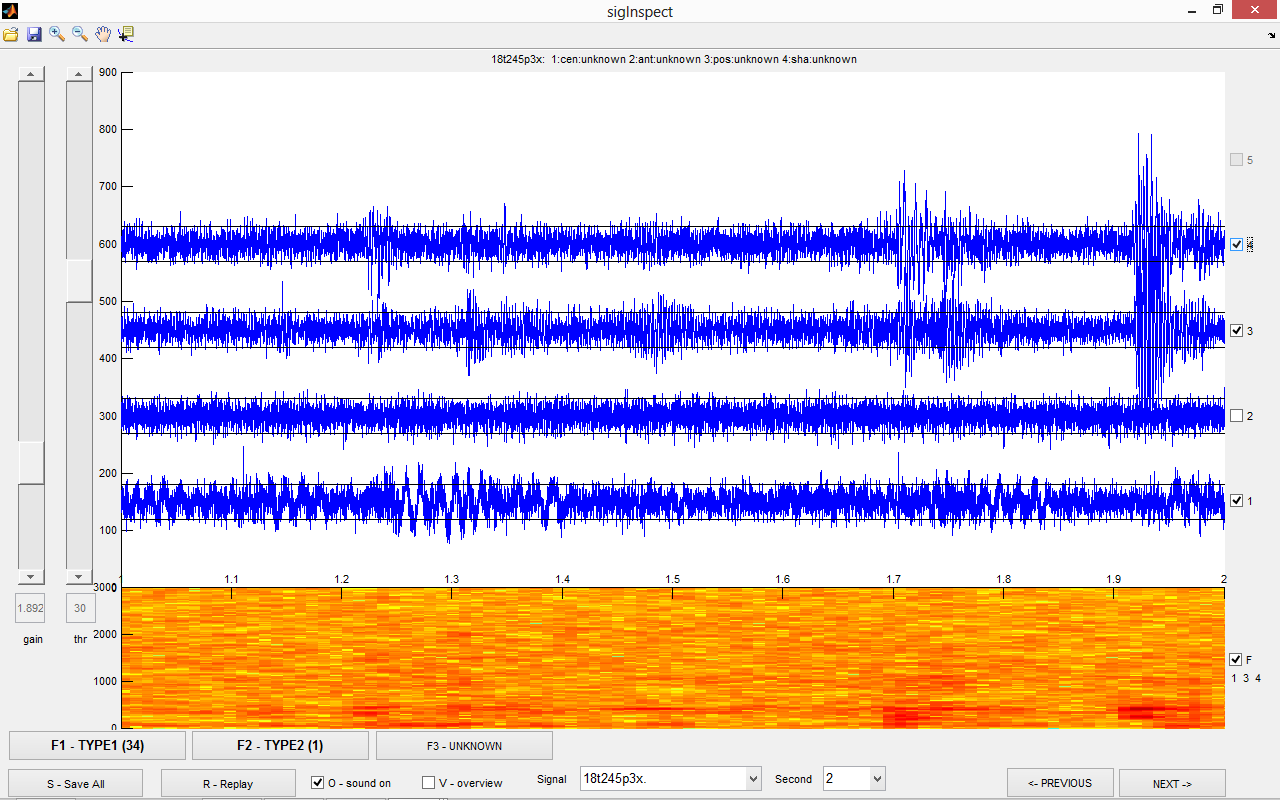

sigInspect is a graphical user interface (GUI) application for Matlab, developed for inspection and

annotation of extracellular microelectrode recordings (MER). The tool allows concurrent visualization of multiple parallel channels, playback and spectrogram plot of selected channels (to identify specific firing patterns) and especially annotation of individual channels. Parallel signals are displayed in one-second segments, which can be easily annotated using the GUI controls or shortcut keys. SigInspect also contains tools for automatic annotation of microelectrode recording data, based on published methods. This can provide starting point for manual annotation and speed up the data-cleaning process considerably.

sigInspect and manual available at github.com/ebakstein/sigInspect